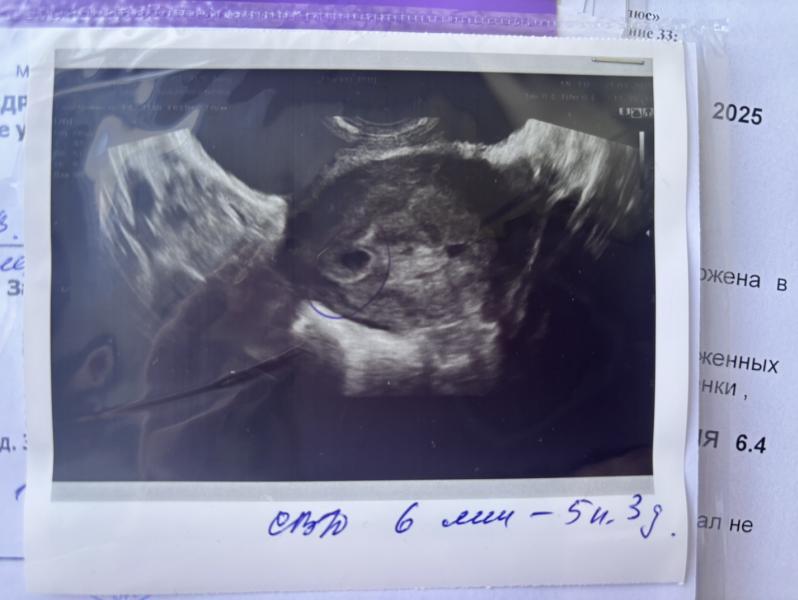

В общем история такая. Самое первое узи мне делали в ПЦ, срок очень маленький, еле увидели плодное яйцо в матке и еще «что-то», (на фото узи видно справа). Плодное яйцо она специально обвила ручкой, а по поводу второго сказала, что может быть второй Лялик, пока не понятно, надо позже смотреть, но потом говорит «Давай гляну через живот?», посмотрела и говорит «да нет, это наверное эндометрий или сосуд, не похоже на плодное яйцо»… ну мне сказали «нет», я и забыла до вчерашнего дня 😄.

На этом снимке я вообще вижу несколько п/я 😅 много тёмных кружков/овалов.

Если есть еще снимки - покажите

Наиболее вероятно что это полость матки не полностью сомкнувшаяся

Тоже был высокий хгч, один в итоге. У вас это врятли пя тк нет ободка вокруг как у первого

По УЗИ непохоже на 2-е плодное яйцо. Нет характерного ободка.

@kinder-nastya в норме плодное яйцо имеет круглую или овальную форму, оно прямо похоже на яйцо по очертаниям🙂

И по всему контуру в любой проекции идёт плотная белая кайма.

Тут такого нет.